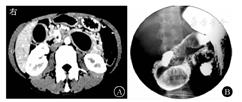

实验室检查:血常规示白细胞计数为3.82×109/L,中性粒细胞占比为0.358,红细胞计数为4.51×1012/L,血红蛋白为118 g/L,血清肿瘤标志物、血生物化学指标、ESR、尿粪常规检查均未见异常。电子胃镜检查示十二指肠降部黏膜下隆起(图1A)。超声胃镜提示十二指肠降部固有肌层低回声病灶(图1B)。上腹部CT增强检查示十二指肠水平部与升部交界处类圆形低密度影,考虑肠重复畸形或肠壁来源囊性良性病变可能性大(图2A)。上消化道钡剂造影检查提示十二指肠降部与水平部交界处外压性充盈缺损,可随肠管蠕动,考虑重复畸形可能性大(图2B)。